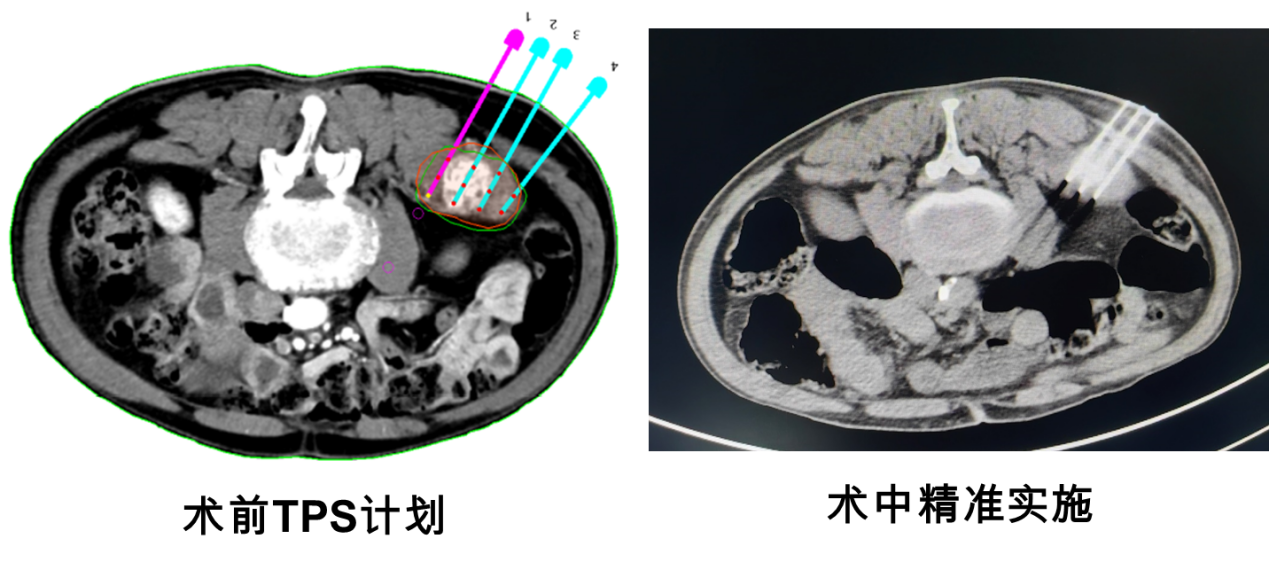

为保障手术治疗效果及安全性,移植外科曲凯副教授、核医学科屈伟副主任及宁宁副主任医师在术前精心勾画治疗靶区,进行TPS计划,以确保粒子精准植入。2023年7月6日,在核医学科郑向红主任的大力支持下,由移植外科曲凯副教授、核医学科宁宁副主任医师在我院核医学科完成首例CT引导下骨转移瘤125碘粒子植入术。在多学科保障及医技护组的积极配合下,手术实施过程顺利,患者术后第二天便可自由翻身、下床,第三天恢复出院。